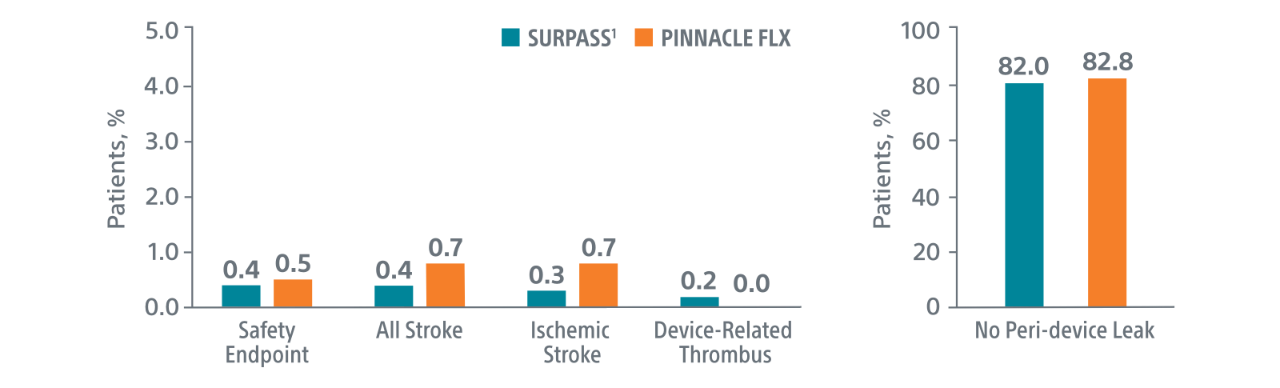

Comparison with PINNACLE FLX2

45-Day Outcomes

PINNACLE FLX

Study Design

- 400 patient, 29 US site, single arm, non-randomized trial evaluating WATCHMAN FLX for non-inferiority to safety and efficacy performance goals based on the WATCHMAN™ device.

- Follow-up: 45 days (+TEE), 6 months, 12 months (+TEE), 18 months, and 24 months

- Patient Characteristics: Average CHA2DS2-VASc of 4.2±1.5, Average HAS-BLED of 2.0±1.0

- Post Implant Drug Regimen: NOAC/ASA for 45 days, Clopidogrel/ASA to 6 months, ASA post 6 months

- Primary Safety Endpoint: All-cause death, ischemic stroke, systemic embolism, or device- or procedure-related adverse events requiring surgery or major endovascular intervention within 7 days following the procedure or by hospital discharge, whichever is later.

- Primary Efficacy Endpoint: The rate of effective LAA closure defined as any peri-device flow ≤5mm demonstrated by TEE at 12 months

- Secondary Efficacy Endpoint: The occurrence of ischemic stroke or systemic embolism at 24 months from the time of enrollment

- Inclusion/exclusion criteria is consistent with WATCHMAN clinical study inclusion/exclusion criteria. Patients must be eligible for short-term NOAC vs warfarin in previous clinical studies.

Primary Safety Endpoints

Primary Efficacy Endpoints

The rate of effective LAA closure defined as any peri-device flow ≤5mm demonstrated by TEE at 12 months.

** Performance goal pased on the rates observed in PREVAIL(1) and CAP2(2), minus a clinically relevant delta